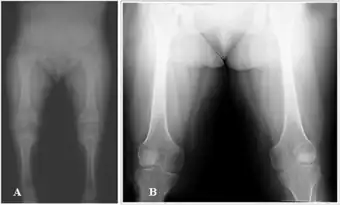

Spondyloperipheral dysplasia is an autosomal dominant[1] disorder of bone growth. The condition is characterized by flattened bones of the spine (platyspondyly) and unusually short fingers and toes (brachydactyly). Some affected individuals also have other skeletal abnormalities, short stature, nearsightedness (myopia), hearing loss, and mental retardation. Spondyloperipheral dysplasia is a subtype of collagenopathy, types II and XI.